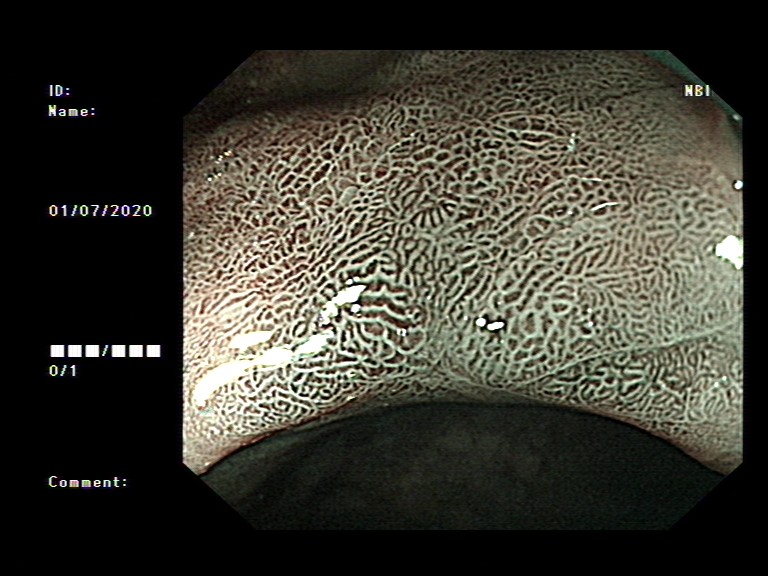

2020年1月,元旦刚过,大家都还沉浸在新年的喜悦中,来自隆安县的张阿姨一家却一筹莫展,张阿姨今年55岁,半年前开始出现上腹部胀痛不适,在当地医院一直按“慢性胃炎”服用中药及西药治疗,症状时好时坏。为了进一步治疗,来到我院就诊,内镜中心袁海锋主任亲自为其进行了无痛胃镜检查,经认真仔细观察发现胃内一处凹陷型病变,进一步行精细胃镜检查后,初步判断为早期胃癌病灶,而且病变侵犯深度局限在粘膜层内。经过与张阿姨及家属详细沟通后,决定用内镜下微创手术为其治疗。在内镜下确定病变边界后,顺利行内镜下粘膜剥离术(ESD)将病变完整切除。术后标本病理提示:早期胃癌(中分化管状腺癌)。治疗后一周,恢复良好,顺利出院,至今随访未诉明显不适。对于张阿姨一家来说,得了胃癌很不幸,但不幸中的万幸,她的胃癌被我们早期及时发现并完成了内镜下切除,避免进展为中晚期胃癌,使原本不富裕的家庭再雪上加霜。

图3 术后病理